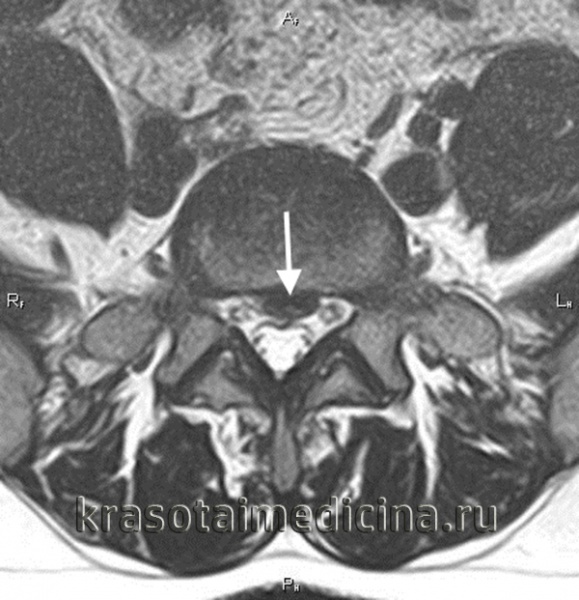

МРТ ШОП. Грыжевые выпячивания дисков в с. С5-С6, С6-С7 кзади, с выраженным сужением позвоночного канала и сдавлением спинного мозга.

МРТ ШОП. Грыжевые выпячивания дисков в с. С5-С6, С6-С7 кзади, с выраженным сужением позвоночного канала и сдавлением спинного мозга